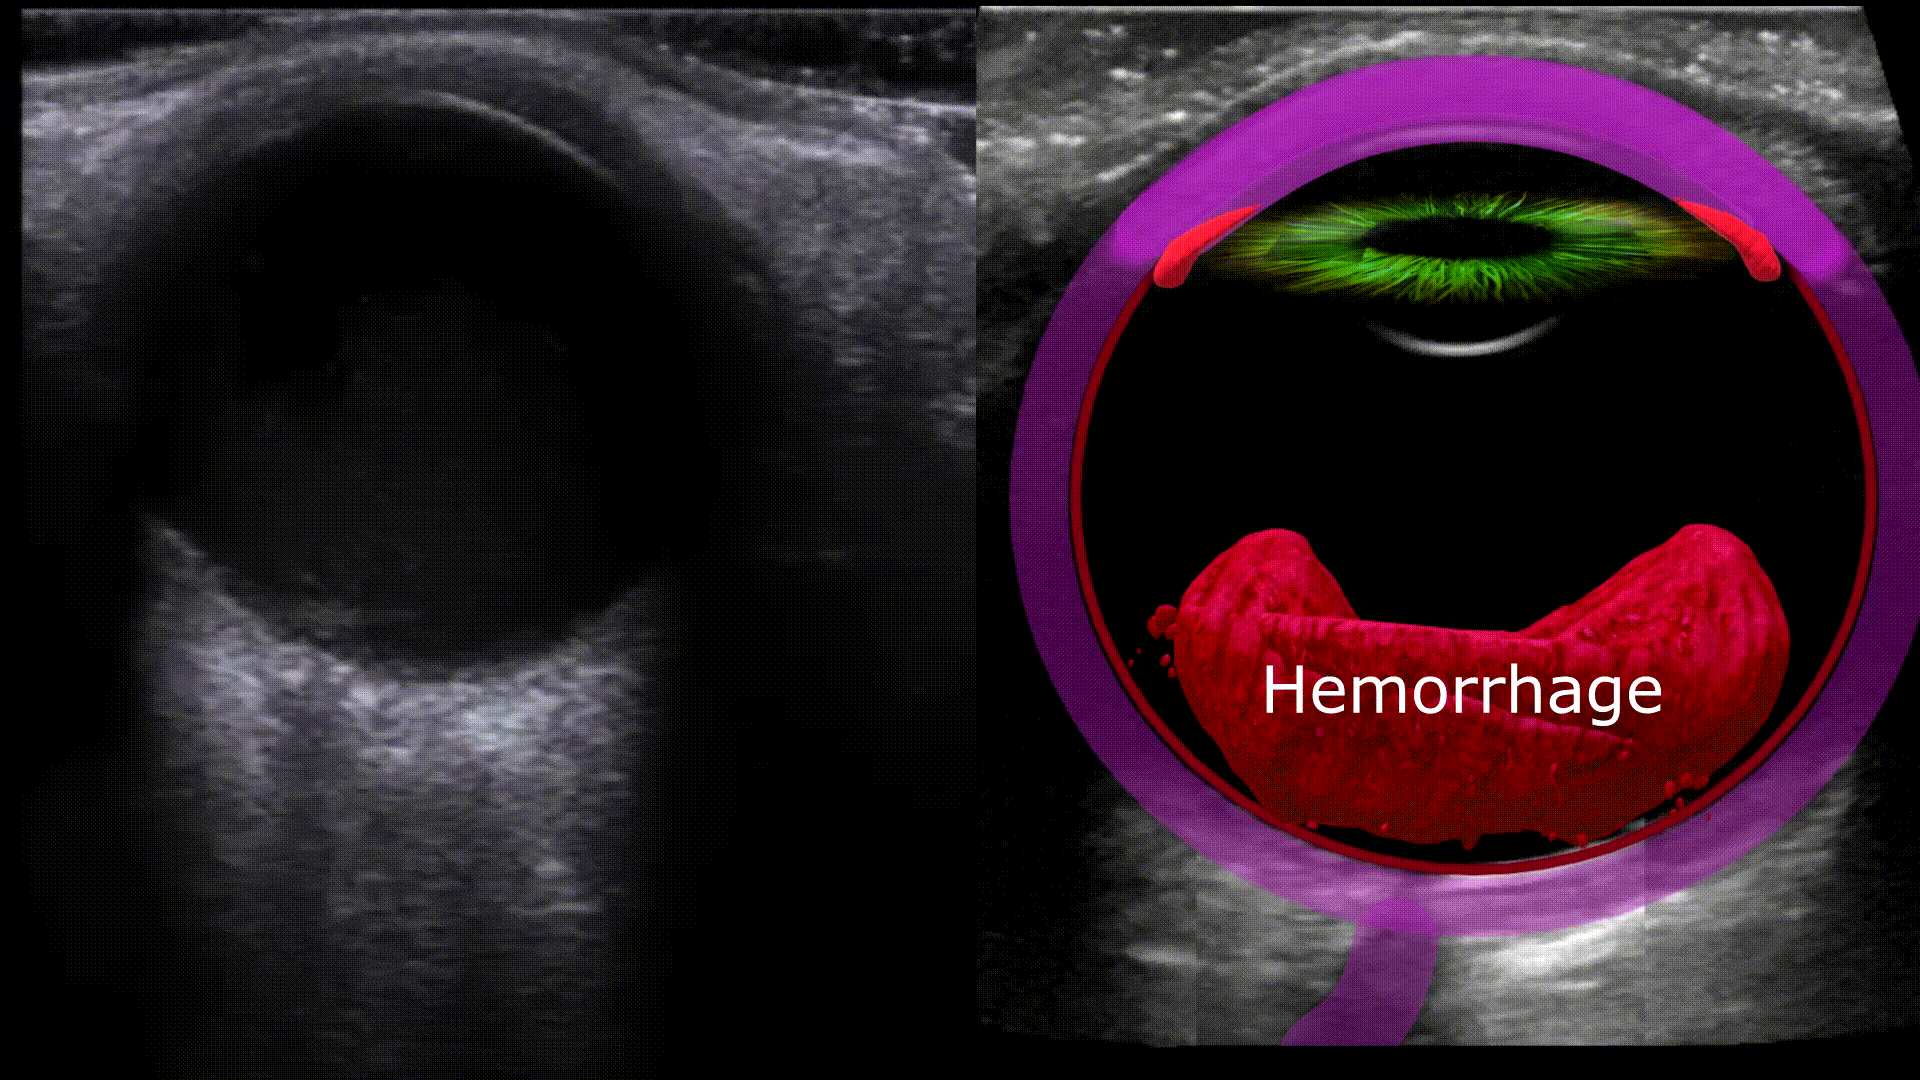

Vitreous Hemorrhage

Any blood located in the vitreous chamber is a vitreous hemorrhage. Usual causes are proliferative diabetic retinopathy, posterior vitreous detachment, and ocular trauma. On ultrasound you’ll see a fluid fluid level within the vitreous chamber with the echogenic fluid representing blood, the echogenicity of the blood will vary depending on acuity (acute less echogenic, chronic more echogenic). The blood will also swish around with eye movements (washing machine sign)

- Diabetic retinopathy

- Trauma

- Retinal tear or detachment

- Posterior vitreous detachment

- Proliferative sickle cell retinopathy

- Age-related macular degeneration